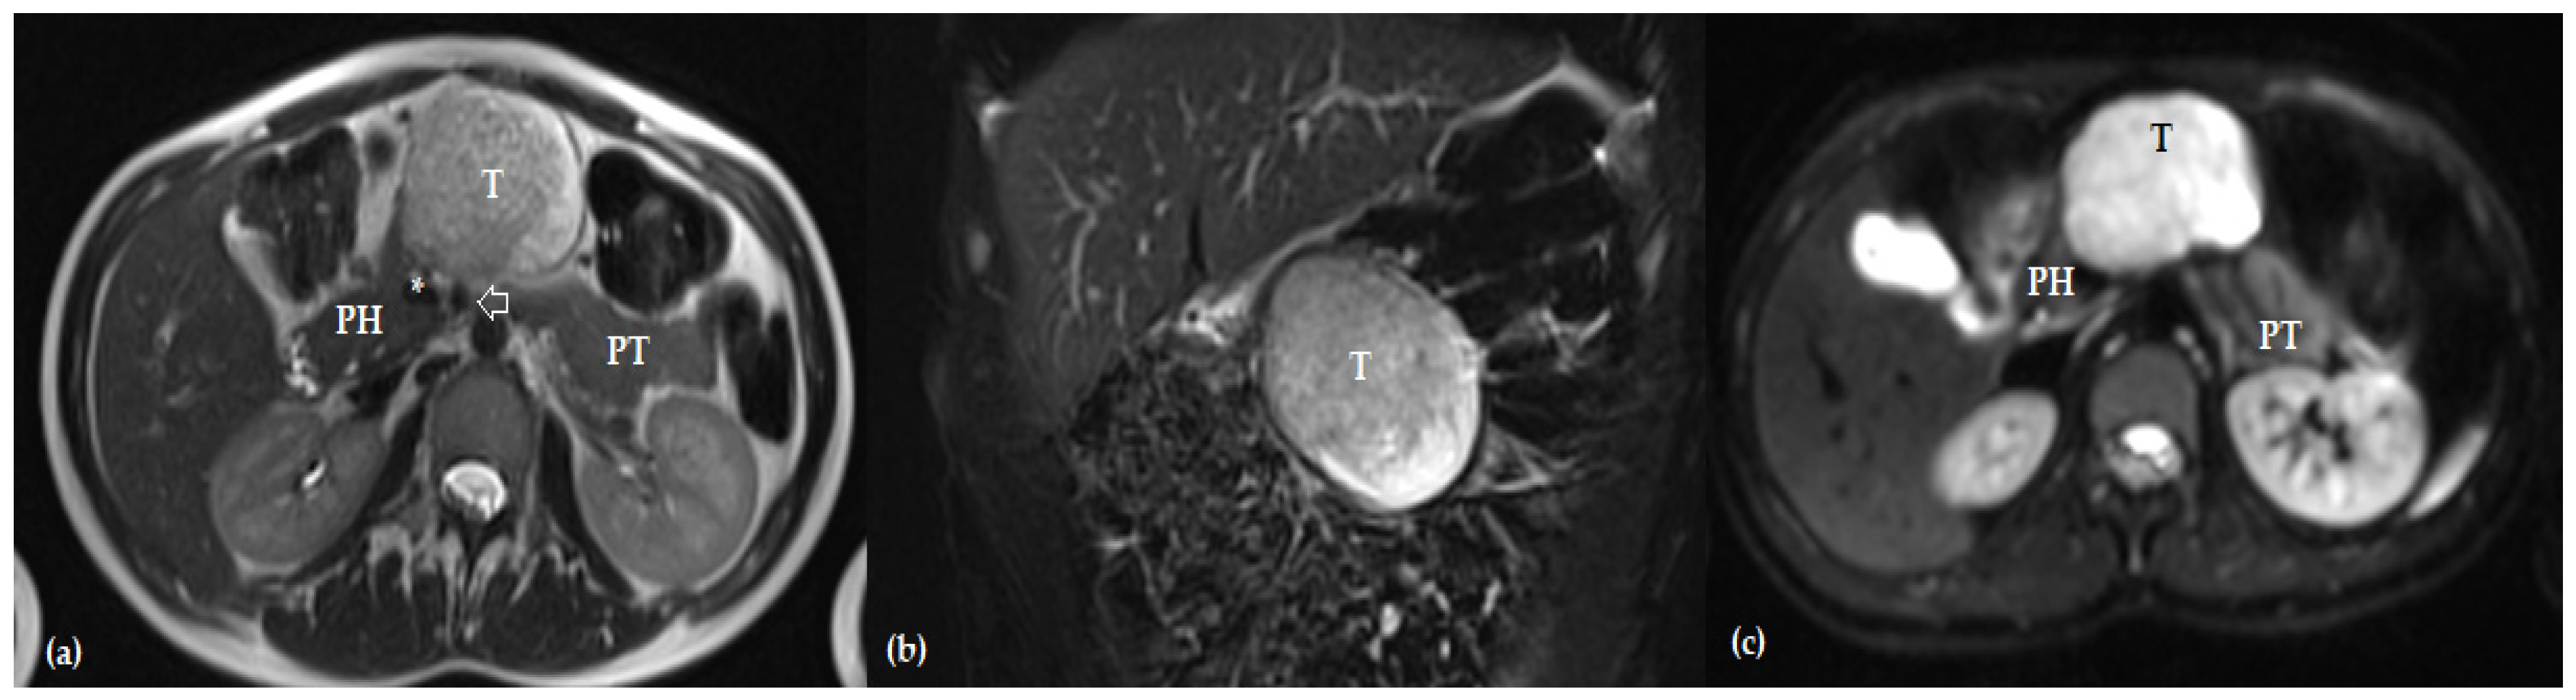

- Dumitrascu, T.; Stanciulea, O.; Herlea, V.; Tomulescu, V.; Ionescu, M. Central Pancreatectomy for Pancreatoblastoma in a 16-Year-Old Girl. J. Pediatr. Surg. 2011, 46, e17–e21. [Google Scholar] [CrossRef] [PubMed]